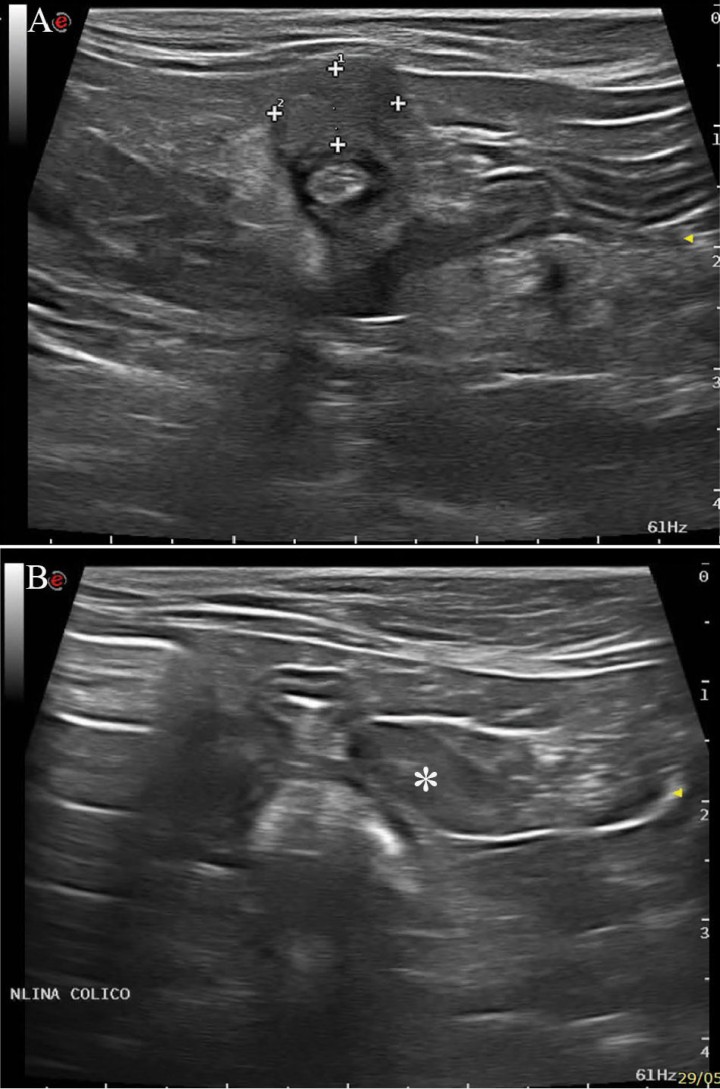

En este caso se realizó, en primer lugar, una ecografía abdominal (Fig. 3), en la que se visualizó en la zona ileocecal una masa excéntrica hipoecogénica, de ecotextura heterogénea, que presentaba un tamaño aproximado de 1 cm x 0,8 cm, con pérdida de visualización de las capas intestinales. La grasa perilesional se observó hiperecogénica y los nódulos linfáticos cólicos se visualizaron ligeramente aumentados de tamaño (1,6 cm de largo x 0,5 cm de ancho) con el ratio eje corto-eje largo de 0,33 (normal ≤0,5). El diagnóstico ecográfico más probable fue de neoplasia intestinal.

<p>Imágenes ecográficas. (<strong>A</strong>) Zona ileocólica en la que se observa una masa excéntrica hipoecogénica y de ecotextura heterogénea (<em>calipers</em>), que presenta un tamaño aproximado de 1 cm x 0,8 cm, con pérdida de visualización de las capas intestinales. (<strong>B</strong>) Nódulo linfático cólico (asterisco), aumentado de tamaño con aspecto ecográfico normal.</p>

Imágenes ecográficas. (A) Zona ileocólica en la que se observa una masa excéntrica hipoecogénica y de ecotextura heterogénea (calipers), que presenta un tamaño aproximado de 1 cm x 0,8 cm, con pérdida de visualización de las capas intestinales. (B) Nódulo linfático cólico (asterisco), aumentado de tamaño con aspecto ecográfico normal.

En el caso de las neoplasias intestinales los signos ecográficos que se observan más frecuentemente son la pérdida de la visualización normal de las capas y el engrosamiento de la pared, hallándose estas alteraciones tanto en el caso del adenocarcinoma como en el del linfoma de células B, que son los tumores más frecuentes en la especie felina.[ Gaschen L: Ultrasonography of Small Intestinal Inflammatory and Neoplastic Diseases in Dogs and Cats. Vet Clin Small Anim 2011; 41:329-344. [PubMed] ] Se pueden diferenciar ecográficamente del linfoma de células T y de las EII en que, en estos casos, suelen preservarse las capas o existir un aumento de grosor de la capa muscular.[ Gaschen L: Ultrasonography of Small Intestinal Inflammatory and Neoplastic Diseases in Dogs and Cats. Vet Clin Small Anim 2011; 41:329-344. [PubMed] ]

Los nódulos linfáticos metastáticos se observan aumentados de tamaño, redondeados e hipoecogénicos, mientras que en la EII pueden aparecer aumentados de tamaño, pero suelen mantener una forma y ecogenicidad normal.[ Gaschen L: Ultrasonography of Small Intestinal Inflammatory and Neoplastic Diseases in Dogs and Cats. Vet Clin Small Anim 2011; 41:329-344. [PubMed] ] En nuestro caso se presentaron ligeramente aumentados de tamaño, aunque conservando el ratio eje corto-eje largo.